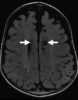

Craniosynostosis Boston type